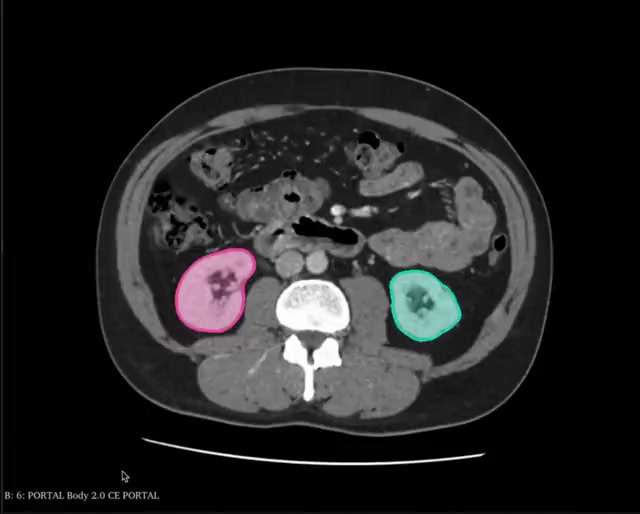

A plataforma organiza automaticamente os dados do paciente — histórico clínico, exames de imagem, modelos 3D e anotações da equipe — criando um dossiê completo para cada caso cirúrgico.

Estratégia cirúrgica documentada com anotações, checklists e referências visuais